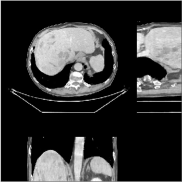

We reconstructed the abdomen volume from low-dose helical CT data. With an initialization of zeros, we ran the PWLS-EP algorithm with and for iterations with subsets for the mA and mA scans, respectively. For PWLS-ULTRA, we chose for the mA scan, for the mA scan, and ran it for outer iterations. The other parameter settings and the transform were the same as those used for the chest scan.

Fig.Β 10 shows the reconstructions (shown for the central axial, sagittal, and coronal planes in the 3D volume) for PWLS-EP and PWLS-ULTRA with patch-based weights () from low-dose abdomen scans. For the sagittal and coronal planes, we show the central out of axial slices. The supplement provides PWLS-EP reconstructions with different regularization strengths. The PWLS-ULTRA reconstructions in Fig.Β 10 have reduced noise as well as higher resolution, better structural details and shaper image edges than the PWLS-EP results. These results are further example of the potential performance of the proposed PWLS-ULTRA method in clinical settings.

Fig.Β 15 provides abdomen reconstructions (shown for the central axial, sagittal, and coronal planes) from low-dose (120kVp, 150mA and 35mA) helical CT data for PWLS-EP with different regularization strengths. We have labeled the reconstruction with good trade-off between image resolution and noise in bold for both doses. These images were used to initialize the PWLS-ULTRA reconstructions in Section IV.F.